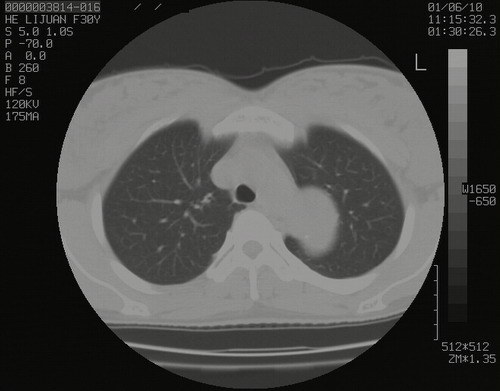

怀孕3个月时(2009-3至4月间),自述突感左侧前后胸疼痛1天,以前胸明显,随后偶感闷痛,余未见异

左肺尖脊柱旁沟肿块,境界清楚,边缘光滑,密度不均,内有多发点片状钙化,考虑良性肿瘤,骨软骨瘤或神经源性肿瘤可能,肺错构瘤不除外。

左后上纵隔见一类圆形肿块影,外侧边界清,密度不均匀,内可见点状钙化影,增强呈不均匀强化,考虑神经源性肿瘤可能。期待病理结果。